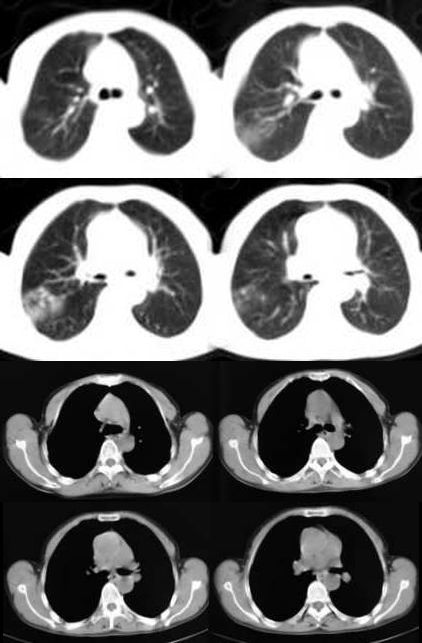

球形肺炎:病变密度相对较淡,中央密度略高,ct图片上密度较为均匀,增强中央可出现无强化区。病变邻近胸膜反应较为显著,可表现为增厚、粘连(可以比较广泛),病变内可以见到大血管的贯穿,周围及近肺门侧可以见到血管纹理增多、增粗,可有支气管充气征象,两侧可垂直于胸膜或呈方形,边缘可为刀切征,它可以出现毛刺样的类似改变,短期内抗炎治疗有效。

炎性假瘤:病灶可呈圆形、椭圆形、三角形、亚铃形等,边缘多比较光滑,密度呈中或偏高密度,周围可有不规则条索影,周围一般无周围充血征象。肿块内可有空洞,可有钙化,但多密度均匀。假性淋巴瘤型可见支气管气相,多为单发,少见多发。肿瘤生长慢,可持续十余年,抗炎可有效果,但阴影不易消散。

(1)发生部位:炎性假瘤可发生在两肺的任何部位,但多位于肺的表浅部位,邻近胸膜处或者靠近叶间裂。可以跨叶生长,原因可能是跨叶浸润的炎症使得假瘤跨叶融合的结果。

(2)假瘤形态:炎性假瘤的形态不一,可呈圆形.椭圆形或类圆形,也可呈驼峰状或不规则图形。

(3)假瘤大小:多数假瘤的直径在2-4cm,也可大于5cm,少数甚至大于10cm.

(4)假瘤密度:炎性假瘤一般为中等密度,密度均匀。而脓性炎症形成的假瘤则有时可见小空洞。空洞可以单发也可多发。少数瘤体切开时可见脓性物。

(5)假瘤边缘:

①有假无假性包膜者边缘清楚。有的由于肿块不规则可表现分叶状。

② 无假性包膜者,假瘤周围有纤维化和多种细胞成分侵润,表现为片状、边缘模糊的团块状影。或有轻度的渗出性病变,边缘模糊,以组织细胞围增生型多见。有的假瘤周围还可以出现类似周围型肺癌的放射冠状表现。

(6)邻近改变:位于肺周边部的假瘤,其邻近胸膜可见局限性粘连增厚。位于近肺门区的假瘤,偶可阻塞支气管,形成肺叶不张而将假瘤包裹,甚似中央性肺癌,但不出现肺门或纵膈淋巴结肿大。